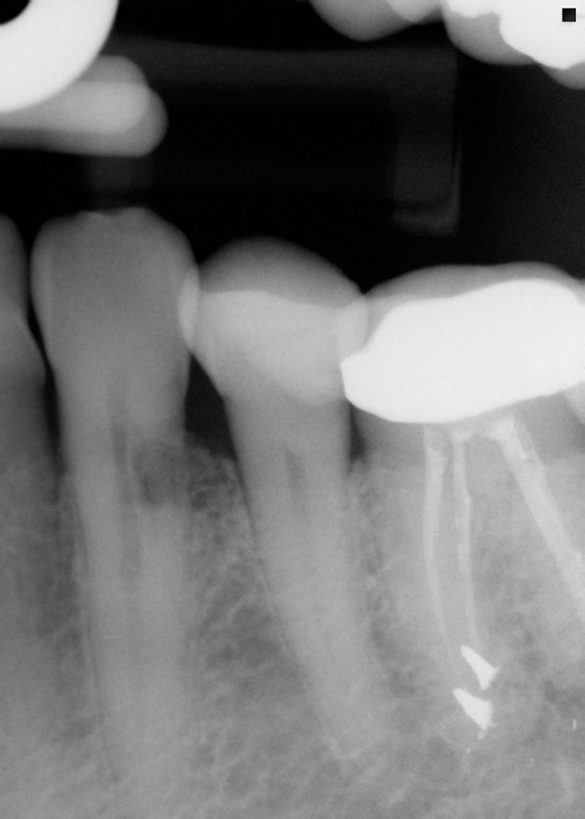

Din cele 109 implante inserate la cei 69 pacienţi în cursul unei perioade de 4 ani, nu s-a înregistrat niciun eşec implantologic după inserţia dispozitivelor fixe şi restaurarea protetică ulterioară. La descoperirea implantelor, nu erau semne de mobilitate a acestora, şi toate implantele inserate au fost restaurate. În momentul prelucrării datelor, toate implantele au rămas complet încărcate şi în funcţiune, rezultând o rată de supravieţuire de 100% (tabelul 1). Ca şi grup, implantele erau funcţionale şi încărcate de o perioadă medie de 2 ani, variind între 6-65 luni. Indiferent de tipul implantului, localizarea în alveolă, statusul de fumător, 100% din implante sunt în funcţiune şi actualmente (tabelul 1 şi fig. 1-9).